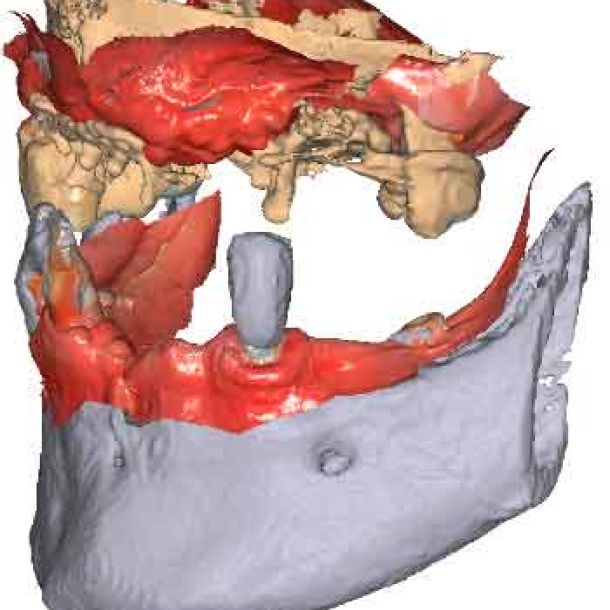

Modèles 3D - Occlusion obtenue par la caméra intra-orale

étape 2 – Acquisition du CBCT

Lorsque les scans IOS traditionnels manquent de références nécessaires, les données du CBCT peuvent servir d'alternative viable. En utilisant les fichiers du CBCT, le clinicien peut établir des références anatomiques précises pour la planification du traitement.

Pour pouvoir utiliser les données CBCT comme modèles initiaux, nous devons transformer le fichier DICOM en un fichier STL. Découvrez-en plus sur la segmentation CBCT et son utilisation dans TWIM ci-dessous.